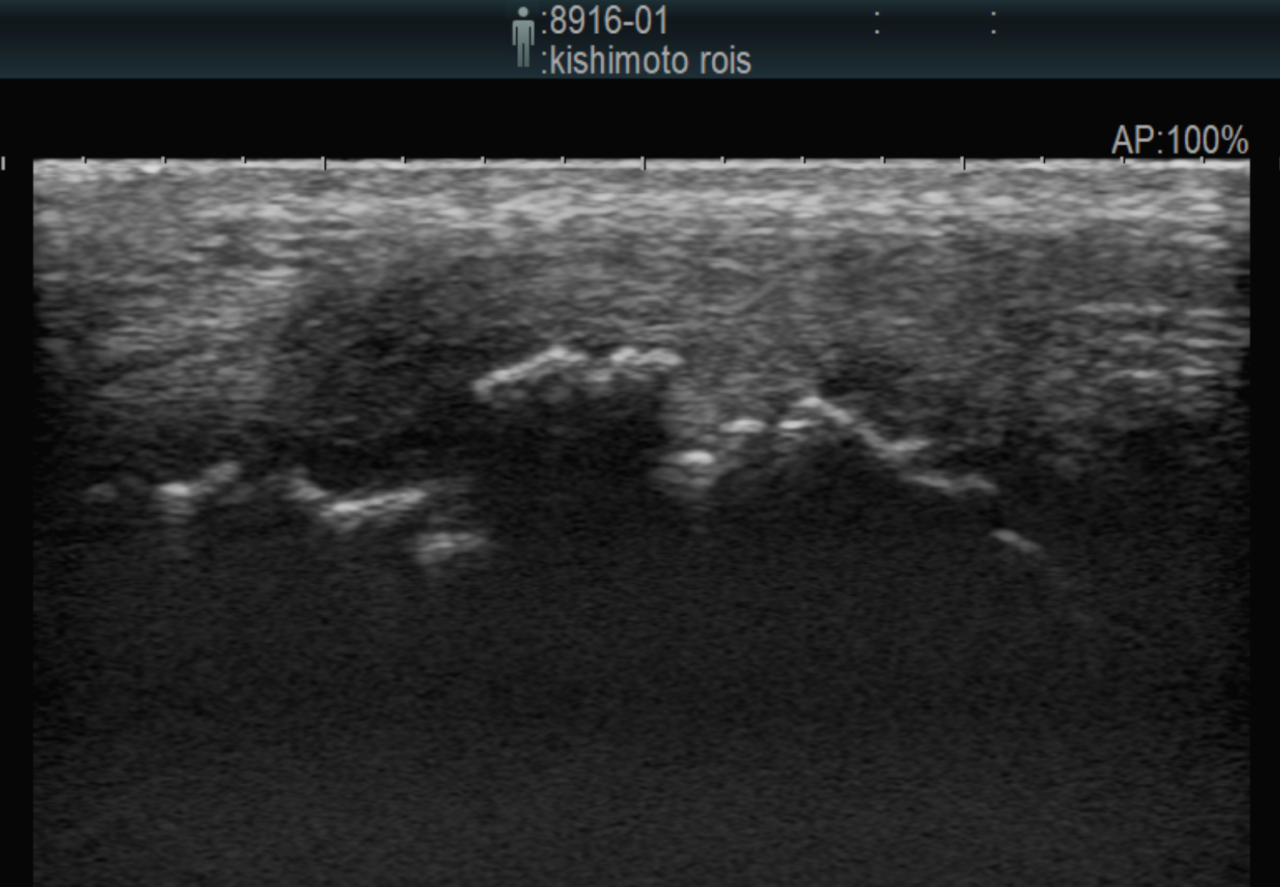

大型犬の前十字靭帯疾患(慢性経過)に対するCBLO #254 大型犬のCrCLDの患者さんに3.5 Rita Locking CBLOで対応しました。今後はリハビリテーションが非常に重要になります。生涯にわたって膝関節のケアを行なっていく必要があります。 症例カテゴリー 放射線治療整形外科軟部組織外科脳神経外科内科腫瘍外科救急・集中治療リハビリテーション科腫瘍内科内視鏡科脳神経科呼吸器外科中医・漢方猫の腎移植循環器科